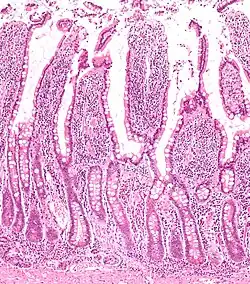

Vilosidades e criptas tingidas com H-E.

Criptas de Lieberkühn ou criptas intestinais são glândulas tubulares simples encontradas entre as vilosidades da parede do intestino delgado e intestino grosso (colon). Secretam diversas enzimas, como sucrase e maltase, e possuem células especializadas na produção de hormônios e enzimas de defesa.[1]

Possuem epitélio simples colunar e fazem parte da camada mucosa do intestino.